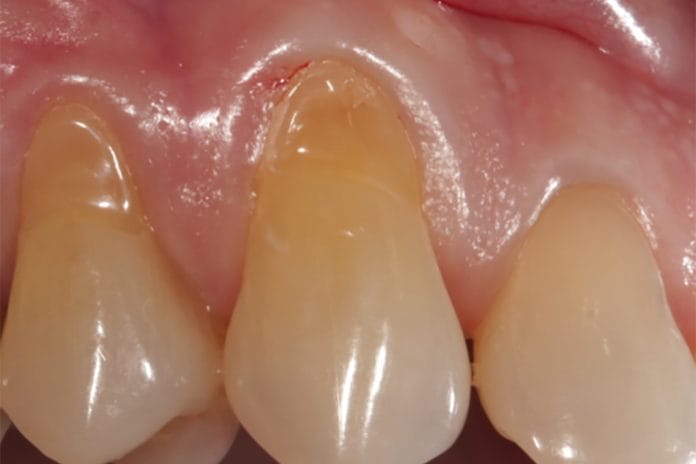

Gingival Recession: When Surgical Options Should be Considered Instead of Patient Education

Gingival recession is something most of us see in our patients’ on a daily basis. It is defined as the apical migration of gingiva,...